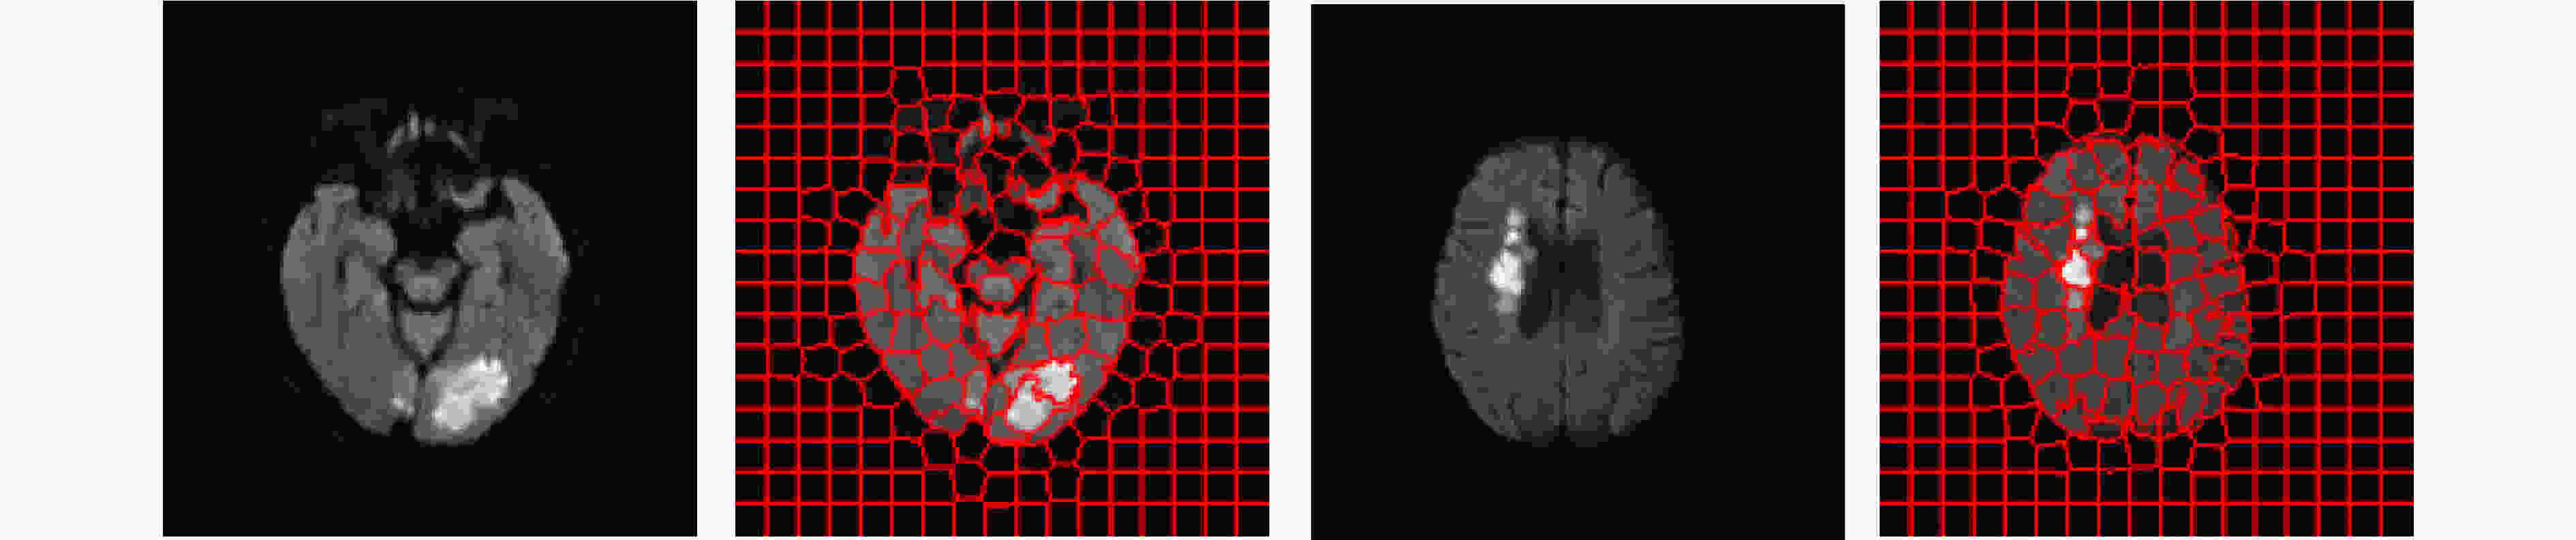

Objective In the clinical management of Acute Ischemic Stroke (AIS), Computed Tomography (CT) and Diffusion-Weighted Imaging (DWI) serve complementary roles at different stages. CT is widely applied for initial evaluation due to its rapid acquisition and accessibility, but it has limited sensitivity in detecting early ischemic changes, which can result in diagnostic uncertainty. In contrast, DWI demonstrates high sensitivity to early ischemic lesions, enabling visualization of diffusion-restricted regions soon after symptom onset. However, DWI acquisition requires a longer time, is susceptible to motion artifacts, and depends on scanner availability and patient cooperation, thereby reducing its clinical accessibility. The limited availability of multimodal imaging data remains a major challenge for timely and accurate AIS diagnosis. Therefore, developing a method capable of rapidly and accurately generating DWI images from CT scans has important clinical significance for improving diagnostic precision and guiding treatment planning. Existing medical image translation approaches primarily rely on statistical image features and overlook anatomical structures, which leads to blurred lesion regions and reduced structural fidelity. Methods This study proposes a Joint Mask and Multi-Frequency Dual Attention Generative Adversarial Network (JMMDA-GAN) for CT-to-DWI image synthesis to assist in the diagnosis and treatment of ischemic stroke. The approach incorporates anatomical priors from brain masks and adaptive multi-frequency feature fusion to improve image translation accuracy. JMMDA-GAN comprises three principal modules: a mask-guided feature fusion module, a multi-frequency attention encoder, and an adaptive fusion weighting module. The mask-guided feature fusion module integrates CT images with anatomical masks through convolution, embedding spatial priors to enhance feature representation and texture detail within brain regions and ischemic lesions. The multi-frequency attention encoder applies Discrete Wavelet Transform (DWT) to decompose images into low-frequency global components and high-frequency edge components. A dual-path attention mechanism facilitates cross-scale feature fusion, reducing high-frequency information loss and improving structural detail reconstruction. The adaptive fusion weighting module combines convolutional neural networks and attention mechanisms to dynamically learn the relative importance of input features. By assigning adaptive weights to multi-scale features, the module selectively enhances informative regions and suppresses redundant or noisy information. This process enables effective integration of low- and high-frequency features, thereby improving both global contextual consistency and local structural precision. Results and Discussions Extensive experiments were performed on two independent clinical datasets collected from different hospitals to assess the effectiveness of the proposed method. JMMDA-GAN achieved Mean Squared Error (MSE) values of 0.0097 and 0.0059 on Clinical Dataset 1 and Clinical Dataset 2, respectively, exceeding state-of-the-art models by reducing MSE by 35.8% and 35.2% compared with ARGAN. The proposed network reached peak Signal-to-Noise Ratio (PSNR) values of 26.75 dB and 28.12 dB, showing improvements of 30.7% and 7.9% over the best existing methods. For Structural Similarity Index (SSIM), JMMDA-GAN achieved 0.753 and 0.844, indicating superior structural preservation and perceptual quality. Visual analysis further demonstrates that JMMDA-GAN restores lesion morphology and fine texture features with higher fidelity, producing sharper lesion boundaries and improved structural consistency compared with other methods. Cross-center generalization and multi-center mixed experiments confirm that the model maintains stable performance across institutions, highlighting its robustness and adaptability in clinical settings. Parameter sensitivity analysis shows that the combination of Haar wavelet and four attention heads achieves an optimal balance between global structural retention and local detail reconstruction. Moreover, superpixel-based gray-level correlation experiments demonstrate that JMMDA-GAN exceeds existing models in both local consistency and global image quality, confirming its capacity to generate realistic and diagnostically reliable DWI images from CT inputs. Conclusions This study proposes a novel JMMDA-GAN designed to enhance lesion and texture detail generation by incorporating anatomical structural information. The method achieves this through three principal modules. (1) The mask-guided feature fusion module effectively integrates anatomical structure information, with particular optimization of the lesion region. The mask-guided network focuses on critical lesion features, ensuring accurate restoration of lesion morphology and boundaries. By combining mask and image data, the method preserves the overall anatomical structure while enhancing lesion areas, preventing boundary blurring and texture loss commonly observed in traditional approaches, thereby improving diagnostic reliability. (2) The multi-frequency feature fusion module jointly optimizes low- and high-frequency features to enhance image detail. This integration preserves global structural integrity while refining local features, producing visually realistic and high-fidelity images. (3) The adaptive fusion weighting module dynamically adjusts the learning strategy for frequency-domain features according to image content, enabling the network to manage texture variations and complex anatomical structures effectively, thereby improving overall image quality. Through the coordinated function of these modules, the proposed method enhances image realism and diagnostic precision. Experimental results demonstrate that JMMDA-GAN exceeds existing advanced models across multiple clinical datasets, highlighting its potential to support clinicians in the diagnosis and management of AIS. -